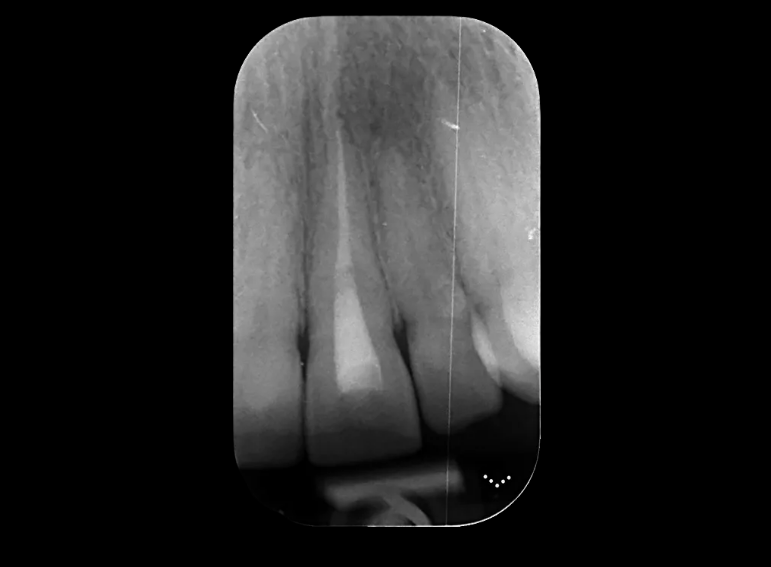

Root canal treatment and combined internal and external whitening.